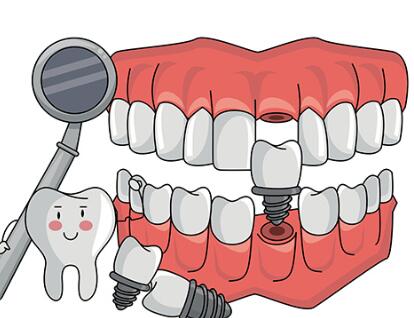

我们每天都在使用牙齿,它们是我们进食、咀嚼的重要工具,也是面部形象的重要一部分。可是,很多人都遇到过牙齿缺损、掉落的情况,这不仅影响了咀嚼功能,也会导致面容失去平衡,甚至引发一些并发症。幸运的是,现在医学发达,通过种植牙技术,我们可以重建完整口腔,恢复理想的咀嚼功能和自信笑容。如果你也在考虑种植牙,那就不要错过下面带来的天津牙科医院种植牙价格表相关内容哦。

在天津,种植牙的价格是许多人挺关心的一个话题。不同的牙科医院,收费自然是不一样的。像是韩国的登腾品牌,一颗种植牙大概需要3780元起;而德国的贝格品牌,价格就得从7000元起。其实,种植牙的总费用不仅仅是看牙齿本身,还有很多其他因素要考虑进去。